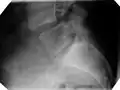

| X-ray of the lateral lumbar spine with a grade III anterolisthesis at the L5-S1 level | |

Classification by degree of the slippage, as measured as percentage of the width of the vertebral body:[14] Grade I spondylolisthesis accounts for approximately 75% of all cases.[6]

- Grade I: 0–25%

- Grade II: 25–50%

- Grade III: 50–75%

- Grade IV: 75–100%

- Grade V: greater than 100%